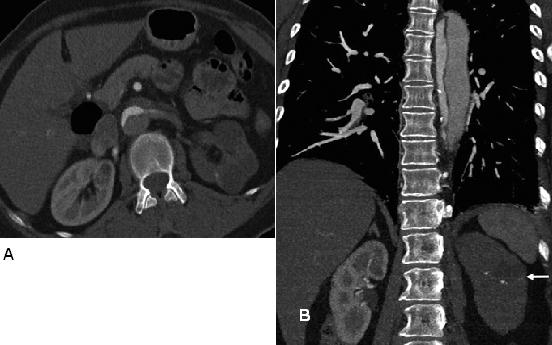

Hình 17: (a) Biến chứng của bóc tách động mạch chủ ngực. Trên Hình axial ngang qua bụng thực hiện ở một bệnh nhân khác, vành bóc tách lòng giả không bắt thuốc chạy lan vào động mạch thận trái và không bắt quang thận trái, một dấu hiệu phù hợp với thiếu máu-nhồi máu nặng. Động mạch thận phải được cấp máu bởi lòng thật và thấy bắt quang bình thường. Ngược lại, trong tắc động, vành lớp áo trong sa xuống qua nguyên ủy động mạch thận, hoạt động như bức màng và bao phủ lỗ động mạch thận. (b) Hình coronal qua bụng cho thấy động mạch thận trái không bắt quang (mũi tên) phù hợp với thiếu máu-nhồi máu thận. Vành bóc tách được nhìn thấy ở động mạch chủ xuống.

Hình 18: Biến chứng của bóc tách động mạch chủ ngực. Hình coronal qua bụng ở một bệnh nhân thứ ba cho thấy vùng giới hạn rõ đậm độ thấp (giảm tưới máu) ở thận trái (mũi tên), một dấu hiệu phù hợp với nhồi máu thận cấp. Vành bóc tách được ghi nhận ở động mạch chủ xuống.